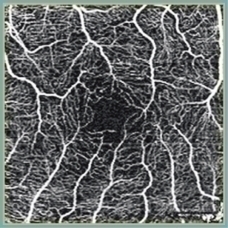

- CT-Angiographyにより、非侵襲で網膜毛細血管を各層別に観察可能(オプション)

12×9mmの撮影範囲内で2種(3/4.5mm)のパノラマ合成を自動でおこなうことが可能です。

スキャン位置は順次移動するため、固視位置を変更することなく撮影できます。

任意設定により5種類(初期設定:網膜全層、表層、深層、外層、脈絡膜)のパノラマが同時に自動合成できます。

網膜全層 HD4 4.5×4.5mm 6枚 パノラマ |

網膜表層 |

網膜深層 |

網膜外層 |

脈絡膜 |